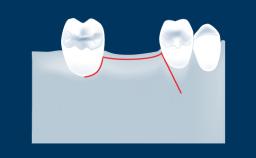

Fatores múltiplos influenciam o sucesso de cirurgias implantares. O que incluem planejamento cuidadoso do tratamento a ser realizado, conhecimento básico de técnicas cirúrgicas comuns a todos os procedimentos cirúrgicos e habilidade de executar estes procedimentos de maneira atraumática. Um destes procedimentos é o fechamento de qualquer retalho gengival que foi rebatido durante a cirurgia. O objetivo do fechamento de retalhos tecidual é reposicionar os tecidos moles gengivais em uma posição anatômica adequada. O fechamento satisfatório do retalho cirúrgico tecidual promove a cicatrização e reduzir complicações como abertura, deiscência e infecção da ferida. Esses fatores desempenham um papel importante na obtenção de resultados cirúrgicos bem-sucedidos e estéticos. Este módulo se concentrará no fechamento do retalho gengival para cirurgia oral relacionada aos procedimentos de implante.

- descrever os princípios cirúrgicos do fechamento de retalhos gengivais após extrações